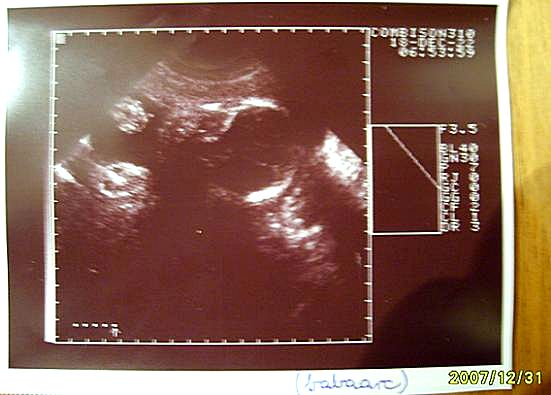

2D Ultrahangok ('07 július - '08 x, Baja)

26+5 Babaarc (07/12/04)